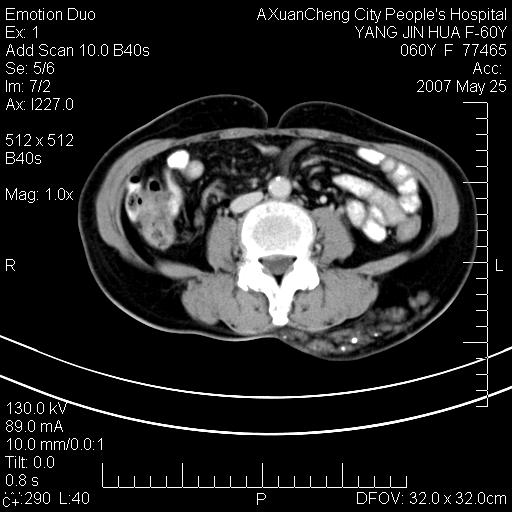

发现左侧腰背部包块40余年,逐渐长大,质软,局部表面可见扩张的血管影

左侧背部皮下混杂密度肿块,结构较疏松,边缘欠光整,内有多发斑点状钙化,考虑:皮下血管瘤。

左背部皮下良性肿瘤,密度不均,边界不清,内有脂肪、钙化,增强扫描无明显强化,血管平滑肌脂肪瘤?进一步诊断有困难,建议穿刺活检。还有,我想还是问一下病史,患者有外伤史吗?能否完全排除外伤后机化的....

血管平滑肌脂肪瘤,支持!另应详细了解病史,待除外骨化性肌炎。

比较典型的左背部皮下血管瘤。

还是考虑皮下血管瘤,强化不明显可能跟大量血栓形成有关,好多战友考虑血管平滑肌脂肪瘤,血管平滑肌脂肪瘤的血管就不强化么?只要有血管就都应该强化。